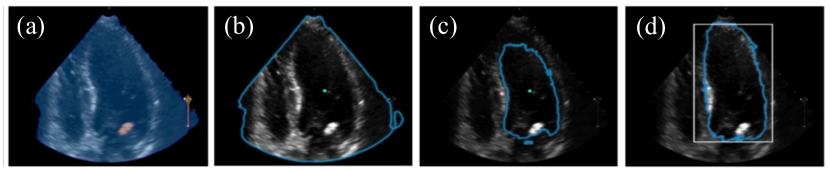

Refer to caption

Figure 4: Qualitative comparison results on different prompts, (a) zero prompt (b) one point (b) two points (d) box prompts, respectively. The green circles indicate the location of the point prompt. The white represents the location of the bounding box prompt. The segmentation results with blue are overlaid on input image.

For CAMUS dataset, all the methods demonstrated comparable segmentation performance for LV endo and LV epi. As detailed in Table 1, our model outperformed the next best method by enhancing the Dice score by 1.9% and 0.2%, and improving the temporal smoothness by 0.03. It’s crucial to recognize the inherent challenges of the CAMUS dataset, which have a high inter and intra-observer variability, reaching up to 6% in the ground truth data [15]. This variability can be further observed in Figure 3 and Table 1. Furthermore, we have included our analysis both SAM-based and non-SAM-based methods. However, for SAM without prompt, and one point prompt, we find they fail to generate plausible results, e.g., w/o prompts generate segmentation of scan of region area totally different from what we want as in Figure 4. Furthermore, when it comes to segmenting for the LVepi𝐿subscript𝑉𝑒𝑝𝑖LV_{epi}, which surrounds the LVendo𝐿subscript𝑉𝑒𝑛𝑑𝑜LV_{endo}, none of the prompt methods achieve successful segmentation. Therefore, we only include the results using two points prompts and box prompts as in Table 1. We presented all results without any post-processing, enabling a direct comparison of segmentation performance.